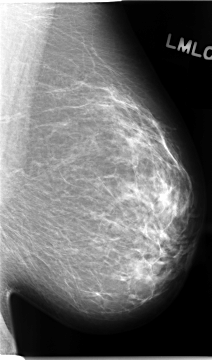

C_0094_1.LEFT_MLO

C_0094_1.LEFT_CC

LEFT_MLO LINES 4680 PIXELS_PER_LINE 2744 BITS_PER_PIXEL 12 RESOLUTION 50 NON_OVERLAY